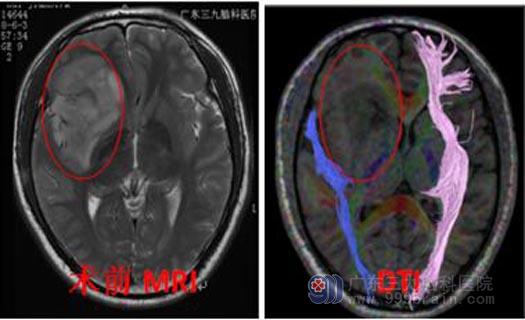

转入广东三九脑科医院行头颅核磁共振检查,提示:右侧额颞岛叶外囊区占位性病变,范围约63mm×77mm×54mm,考虑为弥漫性星形细胞瘤可能性大。完善相关检查后,由鲁明主任主刀行“唤醒麻醉下右侧额颞岛叶占位病变切除术”。显微镜下见肿瘤呈胶冻状,血供丰富,分块次全切除,术腔严格止血,过程顺利,术后病理:肥胖型星形细胞瘤,IDH突变型,WHO II级。